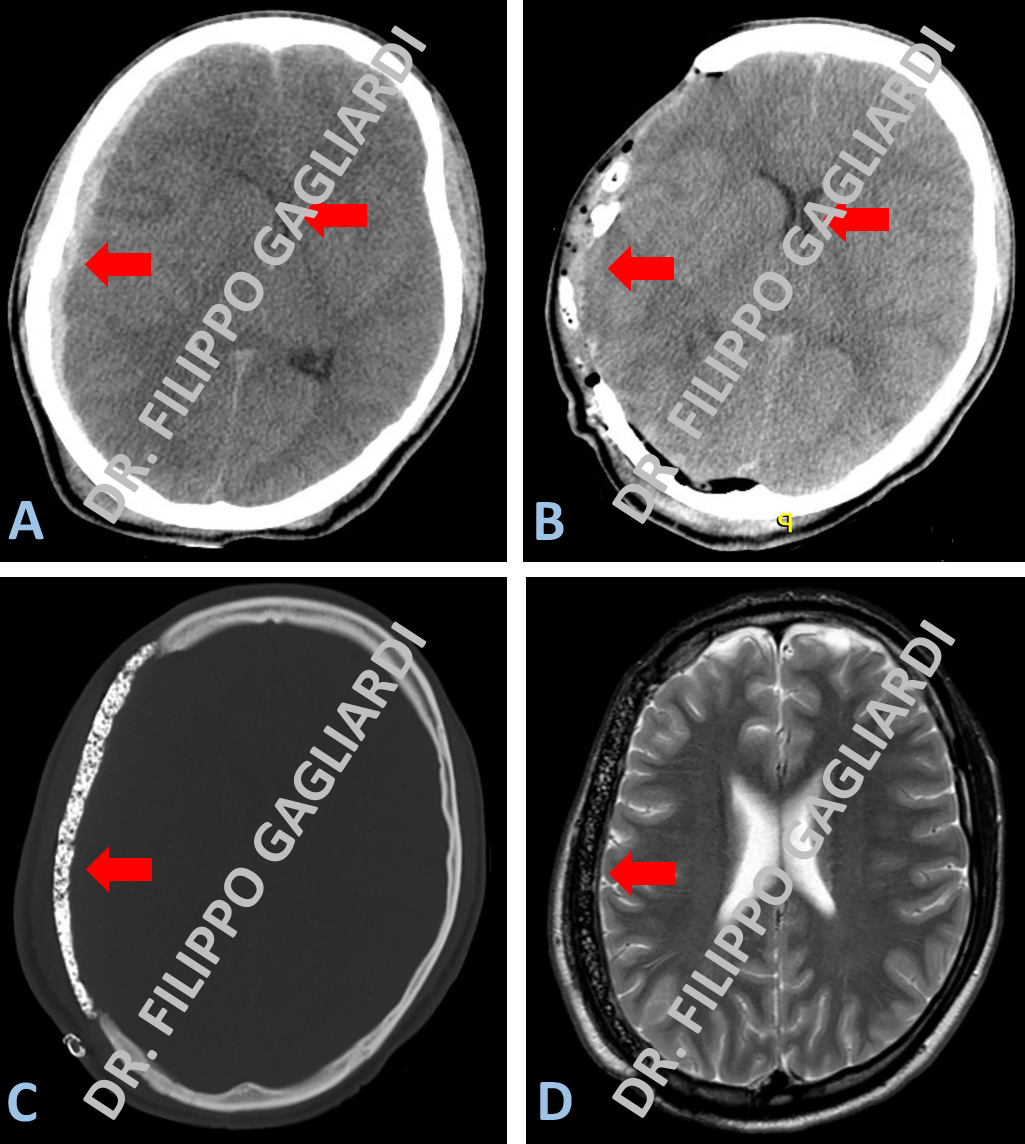

Decompressione osteodurale ed evacuazione di ematoma sottodurale acuto

Caso di ematoma sottodurale acuto post-traumatico. L’emorragia sottodurale, immagine iper-densa (bianca) alla TC, presenta la classica forma a semi-luna. L'ematoma si localizza al di sotto della calotta cranica, esternamente all’emisfero cerebrale di destra e condiziona una compressione critica sull'emisfero cerebrale destro, causando una dislocazione del tessuto cerebrale verso il lato opposto (freccia rossa Figura A). La Paziente è stata sottoposta ad intervento di evacuazione dell’ematoma in regime di emergenza e alla rimozione della calotta cranica (decompressione osteodurale) al fine di ridurre la sofferenza da compressione del cervello gonfio in esiti del noto trauma. La TC post-operatoria (Figura B) mostra gli esiti dell’intervento con la evacuazione completa dell’ematoma e la riespansione del tessuto cerebrale (frecce rosse). Le Figure C e D (frecce rosse) mostrano rispettivamente la TC e la RM encefalo a 6 mesi dal primo intervento dopo la ricostruzione del cranio con l’utilizzo di osso sintetico (cranioplastica).